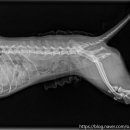

환자들의 후기 등을 미리 살펴보는 것이 도움이 될 수 있습니다. ​ 다음으로, 병원의 시설과 장비 역시 중요한 고려 사항입니다. 최신 진단 장비(예: X-ray, 초음파, 혈액 검사 장비)를 갖추고 있는지, 수술실이나 입원실의 위생 상태는 어떠한지 등을 확인해야 합니다. 특히 응급 상황 발생 시 신속하고 정확한 진단과...

• 선부중앙동물의료센터 | 강아지 요로 결석 재발 재수술 후기

​ ​ ​ 강아지 결석 재발 재수술 후기 강아지 요로결석, 방광결석 재발로 재수술하게 된 후기 남겨봅니다. 반려견 결석은 재발률이 높은 편이라고 해서 꾸준히 관리...이번 수술은 선부중앙동물의료센터에서 진행했어요. ​ ​ ​ ​ 📍선부중앙동물의료센터 정보 주소 : 경기 안산시 단원구 선부광장1로 69 단지내상가동 2층...